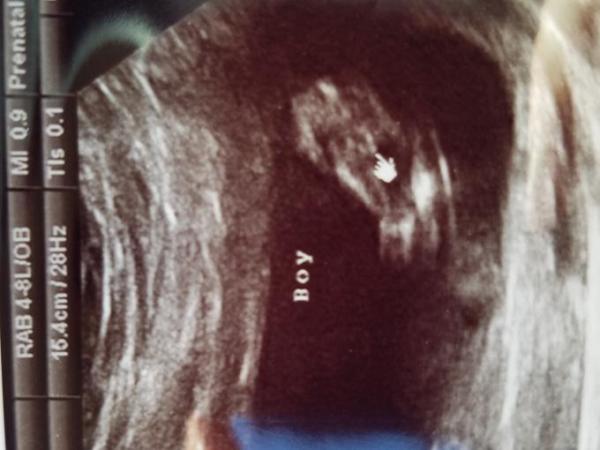

Hallo ihr lieben, ich war am Montag bei meinem FA zum ganz normalen Ultraschall. Der kleine war ziemlich aktiv und sie meinte mal schauen ob wir zwischen die Beine gucken können. Dazu muss ich sagen da war ich 13+4. Sie meinte es sieht wohl sehr danach aus das es ein Junge wird. Hatte das jemand von euch vielleicht auch und kann man sich darauf so gut es geht verlassen? Ich finde es nämlich schon ziemlich früh das jetzt schon festzustellen. Hab hier noch mal das Ultraschall Bild dran gehangen.

13+2ssw

Bild zu